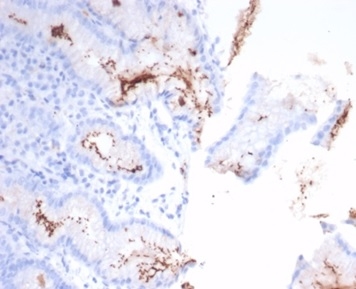

The spiral shaped bacteriumHelicobacter pyloriis strongly associated with inflammation of the stomach and is also implicated in the development of gastric malignancy.H. pyloriis known to cause peptic ulcers and chronic gastritis in human. It is associated with duodenal ulcers and may be involved in development of adenocarcinoma and low-grade lymphoma of mucosa associated lymphoid tissue in the stomach.This antibody stains the individual H. pylori bacterium when it presents on the surface of the epithelium or in the cytoplasm of the epithelial cells in biopsy tissue sections from the antrum and body of the stomach.

Helicobacter pylori infected stomach biopsy